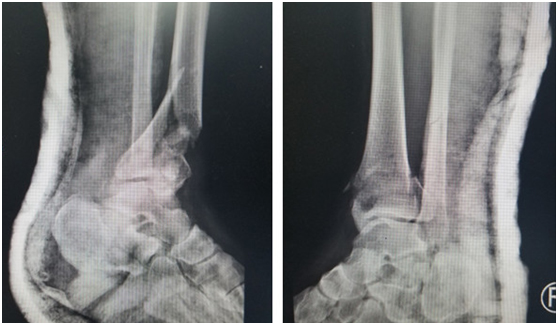

(術前)

在仁慈醫(yī)院,急診醫(yī)生給華大姐完善各項檢查,發(fā)現(xiàn)她的傷情很嚴重:雙pilon骨折,雙跟骨骨折,腰椎多發(fā)骨折。急診醫(yī)生立刻聯(lián)系足踝科徐明亮主任前來會診,徐主任仔細檢查了華大姐的病情,安排她先進行距骨牽引,消腫一周,等待合適的手術時機。

“病人雙側(cè)跟骨粉碎性骨折,脛骨遠端粉碎性骨折,受傷暴力大,周圍軟組織損傷也比較重,短時間內(nèi)局部出現(xiàn)張力性水泡,早期切開后,一是容易導致傷口難以縫合,另外也增加了感染的機會,所以要在消腫以后,再給她切開復位內(nèi)固定,減少患者傷口感染的幾率。”徐明亮主任說。